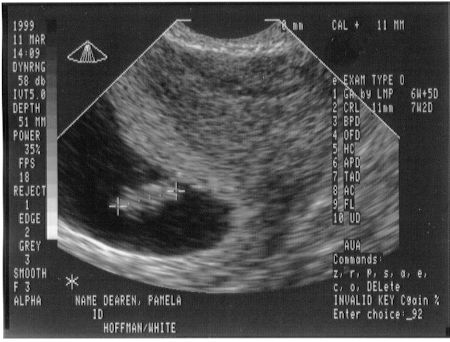

This is me at 7 weeks and 2 days. Mom and Dad got to see my heart beating for the first time.